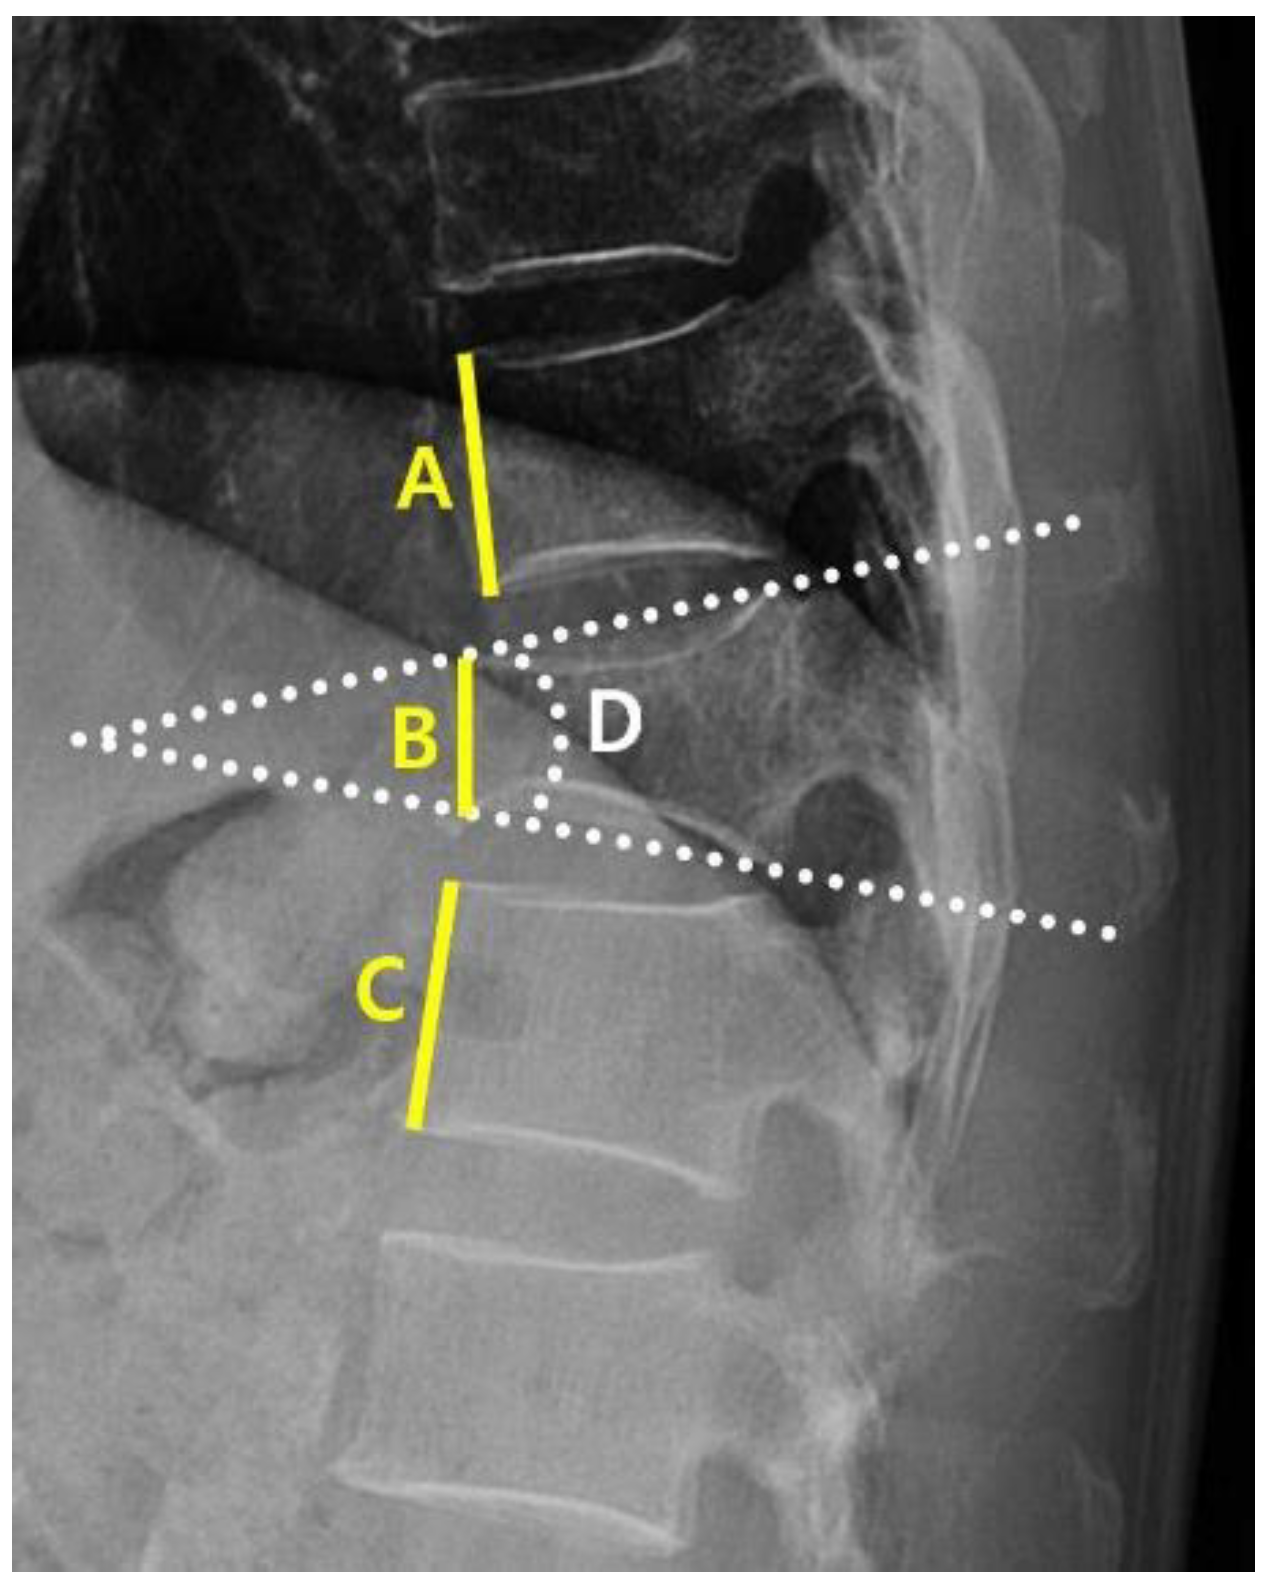

A clinical data warehouse (CDW) containing all medical records from the institution was used to select and study patients. Demographic and radiological data were collected from all enrolled patients. The demographic data included sex, age, diabetes, hypertension, adrenal insufficiency, hyperthyroidism, hypothyroidism, and steroid use. Radiological characteristics were measured using the following variables: the “angle” (local kyphotic angle) and compression ratio of the VCF were measured from the lateral view of the plane radiograph (PR) (Figure 2). From the axial view of MRI, the cross-sectional areas (CSA) of the VCF location and multifidus (MF) and erector spinae (ES) muscles were measured. Additionally, the percentage of fatty infiltration in MF (MFfi) and ES (ESfi) was measured using the imaging pre-processing ImageJ software (version 1.8.0) (Figure 3). In this study, relational multifidus (rMF) was defined as the MF/CSA of the endplate, and relational erector spinae (rES) was defined as the MF/CSA of the endplate.

Figure 2. Measurement of kyphotic angular and compression value. The kyphotic angular and compression value are measured within the picture archiving and communication (PACS) system PR lateral view; D shows the kyphotic angle of the T11 fracture; the compression value is calculated as ((A+C)/2)-B)/ ((A+2)/2).